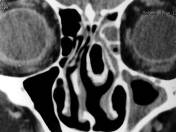

Observamos el examen tomográfico computarizado en plano coronal con alteración anatómica en el complejo ostiomeatal izquierdo (cornete medio neumatizado

o concha bullosa) determinando obstrucción y sinusitis crónica.

No obstante esta alteración anatómica se encuentran no sólo en los pacientes con sinusitis crónica sino también en los controles sanos (54% vs 50%).